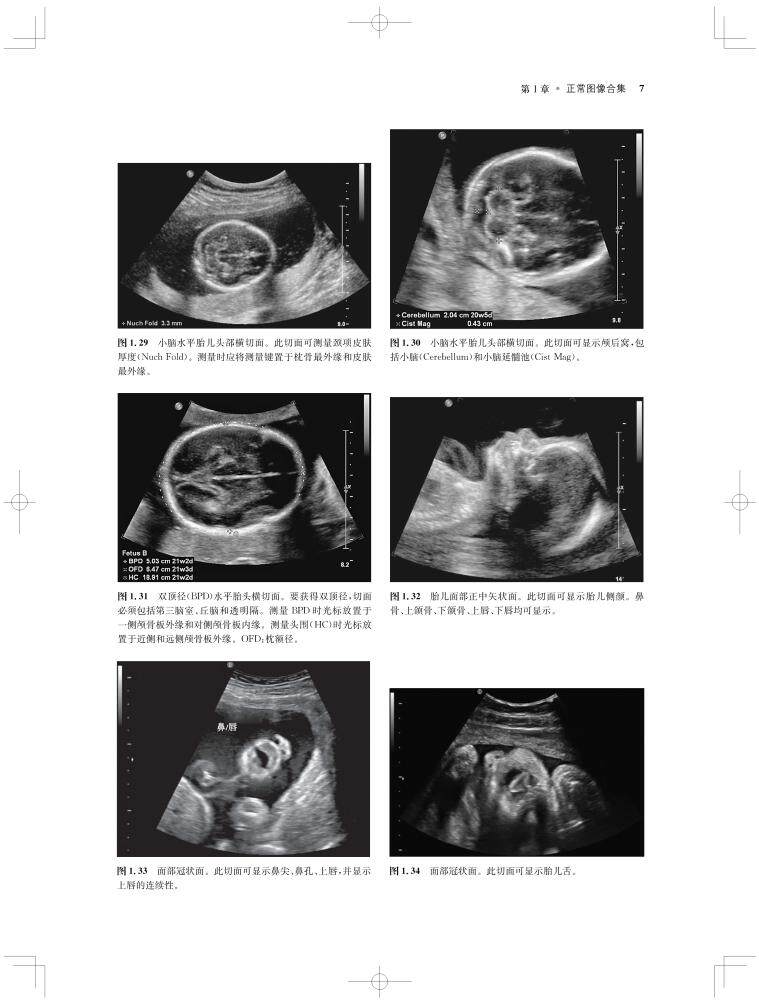

内容涵盖了胎儿宫内疾病的所有病种,从疾病的概述、流行病学、病因学、病理生理学,到临床表现、各类影像学技术的诊断和鉴别诊断,再到产前、产后的治疗和干预手段,都做了全面介绍,重点阐述了疾病的超声、X线、CT、MRI、PET、CT等影像学表现,以及诊断与鉴别诊断,并辅以大量标准化的影像学图片,图文并茂。

《产科影像学——胎儿诊断和监护》是Elsevier(Saunders)出版的“Expert Series”之一,由国际最顶尖的妇产科、生殖科、母胎医学和影像学专家共同编写,代表着该领域最顶尖的水平。书中配有大量典型影像图片,内容丰富全面,编写理念先进,侧重于疾病的影像学征象分析及鉴别诊断和诊断流程的制定,从临床思维上进行了更新;同时兼顾临床和病理医师,重点内容以列表、提要、要点的形式进行总结,提纲挈领,方便读者阅读、记忆。对于每天不断进行诊断与鉴别胎儿疾病的影像工作者、病理科和临床医师而言,具有重要的参考价值。